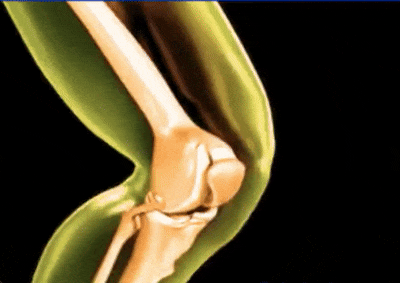

По време на прегледа откриваме ясни признаци на дегенерация на ставите.

❌ Хирургически намеси са необходими, ако ставата напълно откаже. Лекарите извършват операция и заменят ставата с ендопротеза.

При пълна деградация на ставата операцията е неизбежна. След това еластичността на тъканите никога няма да бъде същата.